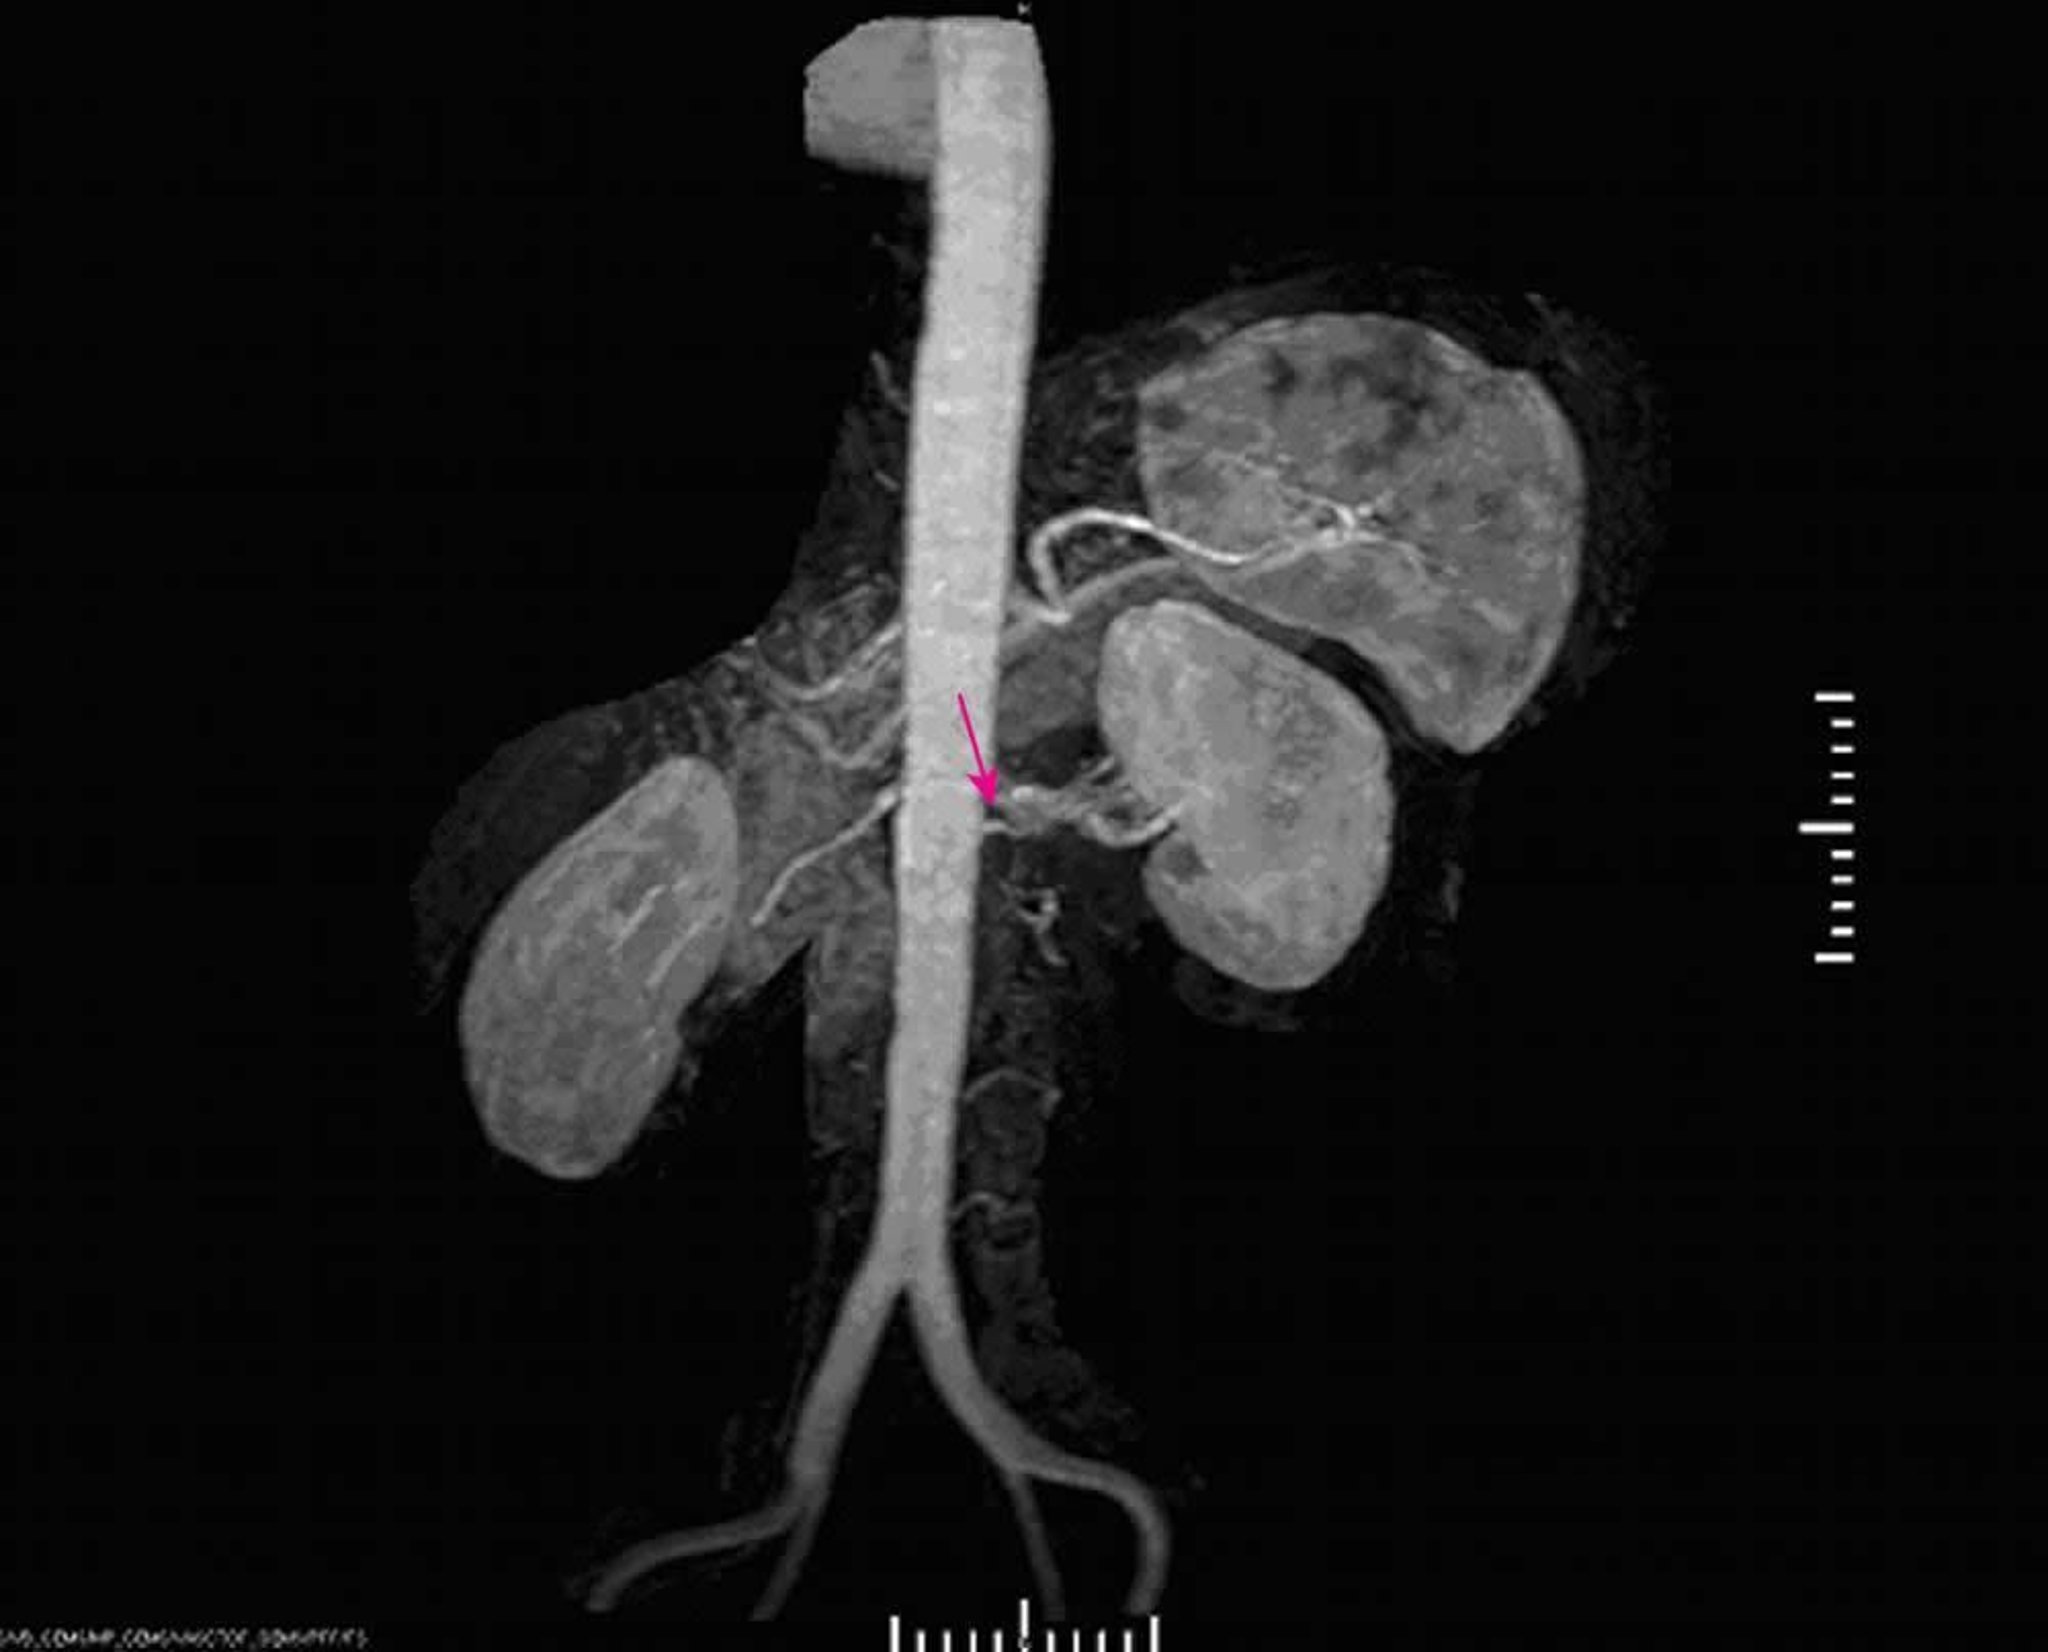

Renovaskuläre Hypertonie (Magnetresonanzangiographie)

Die Magnetresonanzangiographie zeigt eine schwere Stenose am Ursprung der linken Hauptnierenarterie.

Image provided by Jan N. Basile, MD.